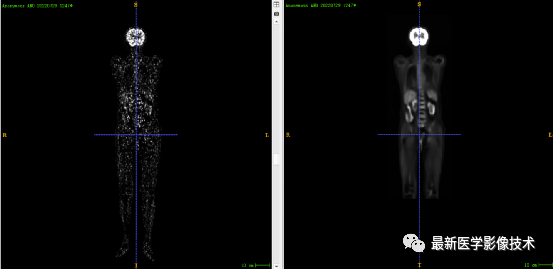

8、测试集重建结果

左图是低剂量图像,右图是重建图像结果。